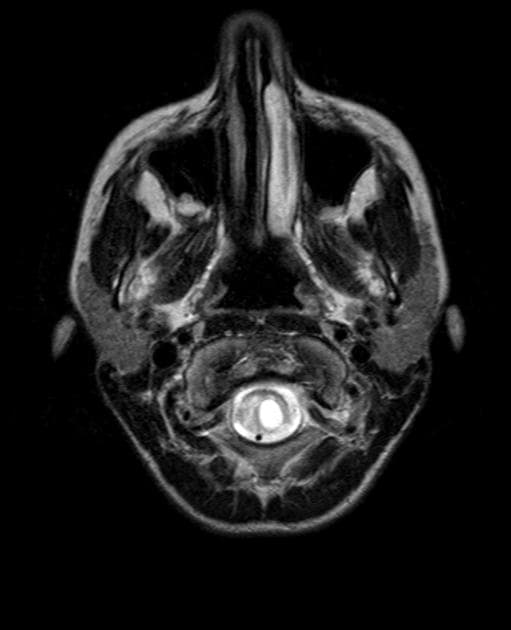

Có tăng tín hiệu nội tủy sống trên các dãy xung T2 và STIR, chủ yếu ảnh hưởng đến chất xám trung tâm, từ mức T8-T9 xuống đến tận tủy hình nón (conus medullaris). Ở một số đoạn, tín hiệu bất thường nội tủy có dạng "owl's eye appearance" (dấu hiệu mắt cú).

Có mức độ giãn nở nhẹ tủy sống.

- "Dấu hiệu 'mắt cú' trên cộng hưởng từ T2 là hình ảnh đặc trưng trong thiếu máu tủy sống, phản ánh sự tổn thương ưu tiên vùng chất xám trung tâm."